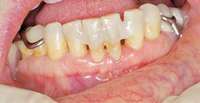

Under the sextant approach, one quadrant is treated and the patient is left to heal for 2 months before proceeding to any additional quadrants. While the patient heals, a 10-day course of antibiotics and 2 months of twice-daily chlorhexidine rinsing may be prescribed. Figure 4 shows a patient who was taking oral bisphosphonates for 3 years and was treated with the sextant approach. As seen in the radiograph, the patient has one molar in the lower right quadrant. This tooth was extracted and the patient was given 2 months to heal (Figure 5 and Figure 6).The patient was placed on antibiotics and chlorhexidine rinse. After 2 months, no signs of BRONJ were observed, and the anterior teeth were scheduled for extraction. They were extracted as atraumatically as possible, and the site was sutured (Figure 7 and Figure 8).The patient then was given another 2 months to heal, following the previous protocol.After 2 months of healing, no BRONJ was observed (Figure 9).

Then, patient was able to move forward with the prosthesis. Figure 10 shows a periodontal patient who was taking oral bisphosphonates for osteoporosis. The patient had full-mouth scaling and root planing, then was given 2 months to heal and instructed to rinse with chlorhexidine twice daily. After no signs of BRONJ were observed, the patient had full-mouth osseous surgery on her few remaining teeth in the mandible. The surgery was performed all at once and not according to the sextant approach because the patient was on a heart and lung transplant list and was moved up the list while healing from the scaling and root planing.

Figure 4 Radiograph of oral bisphosphonate user. Figure 5 and Figure 6 After 2 months of healing, the lower right quadrant showed no signs of BRONJ and the anterior teeth were scheduled for extraction. Figure 6

Figure 9 For this quadrant, no signs of BRONJ were observed after 2 months of healing.

Figure 10 Patient who takes oral bisphosphonates and suffers from periodontal disease.